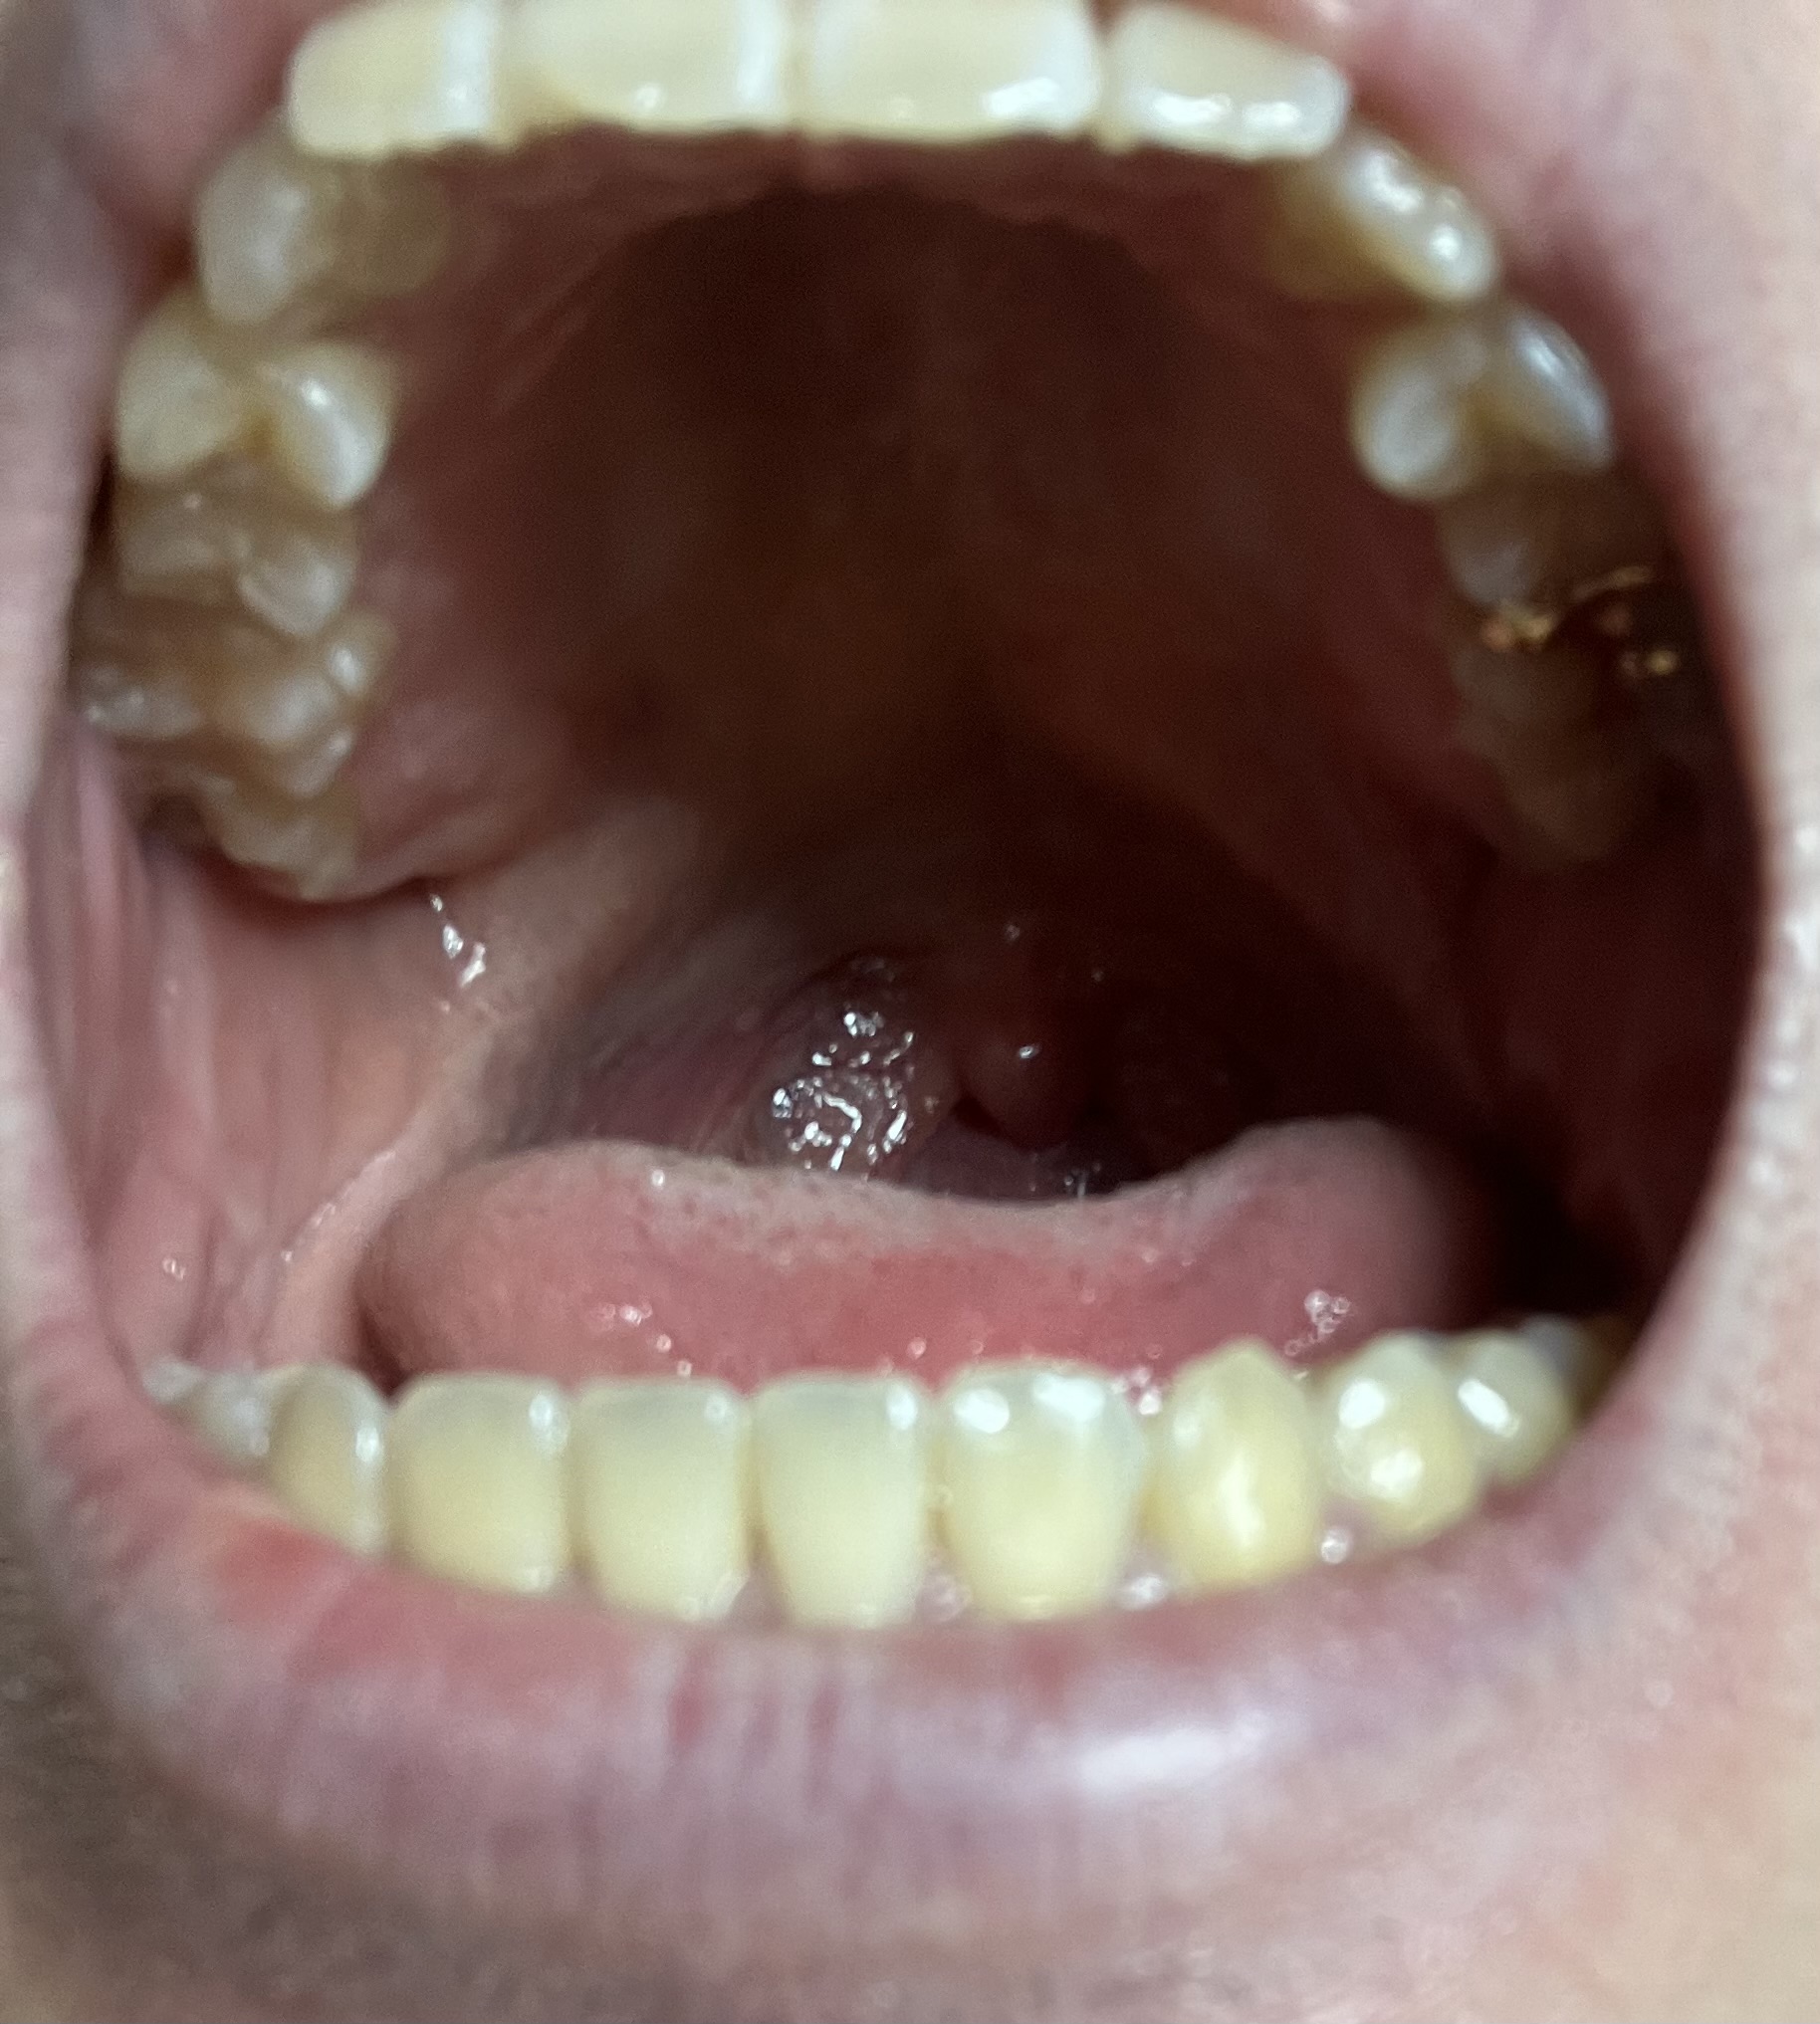

1日3回10分以上かけて歯磨きしてるから綺麗だ

夜はデンタルフロスもやっている

60無念Nameとしあき26/03/23(月)13:41:00No.1395821991そうだねx7

>ID:sHgjYyX6

うんこ臭

>No.1395821873

1日3回はすごいな

俺は晩御飯の後にフロスと歯磨きするだけだわ